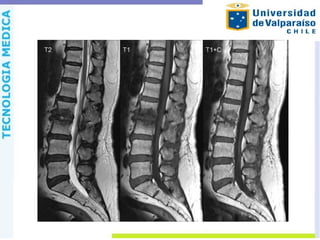

Espondilodiscitis Compromiso infeccioso delcuerpo y disco intervertebral, por diseminación hematógena, a través del plexo venoso de Batson o por contigüidad. Lo más frecuente es la afectación de la columna lumbar, en varones entre 50-70 años y con presencia de S. aureus.

RM Sensibilidad 96%. Exactitud94% Las características incluyen o Discos de alta señal en T2 o Cuerpos vertebrales de baja señal T1 o Realce de contraste de los discos y los cuerpos vertebrales o Realce de contraste de la masa de tejidos blandos paravertebrales o Realce de contraste de absceso paravertebral del psoas o Realce de contraste de absceso epidural